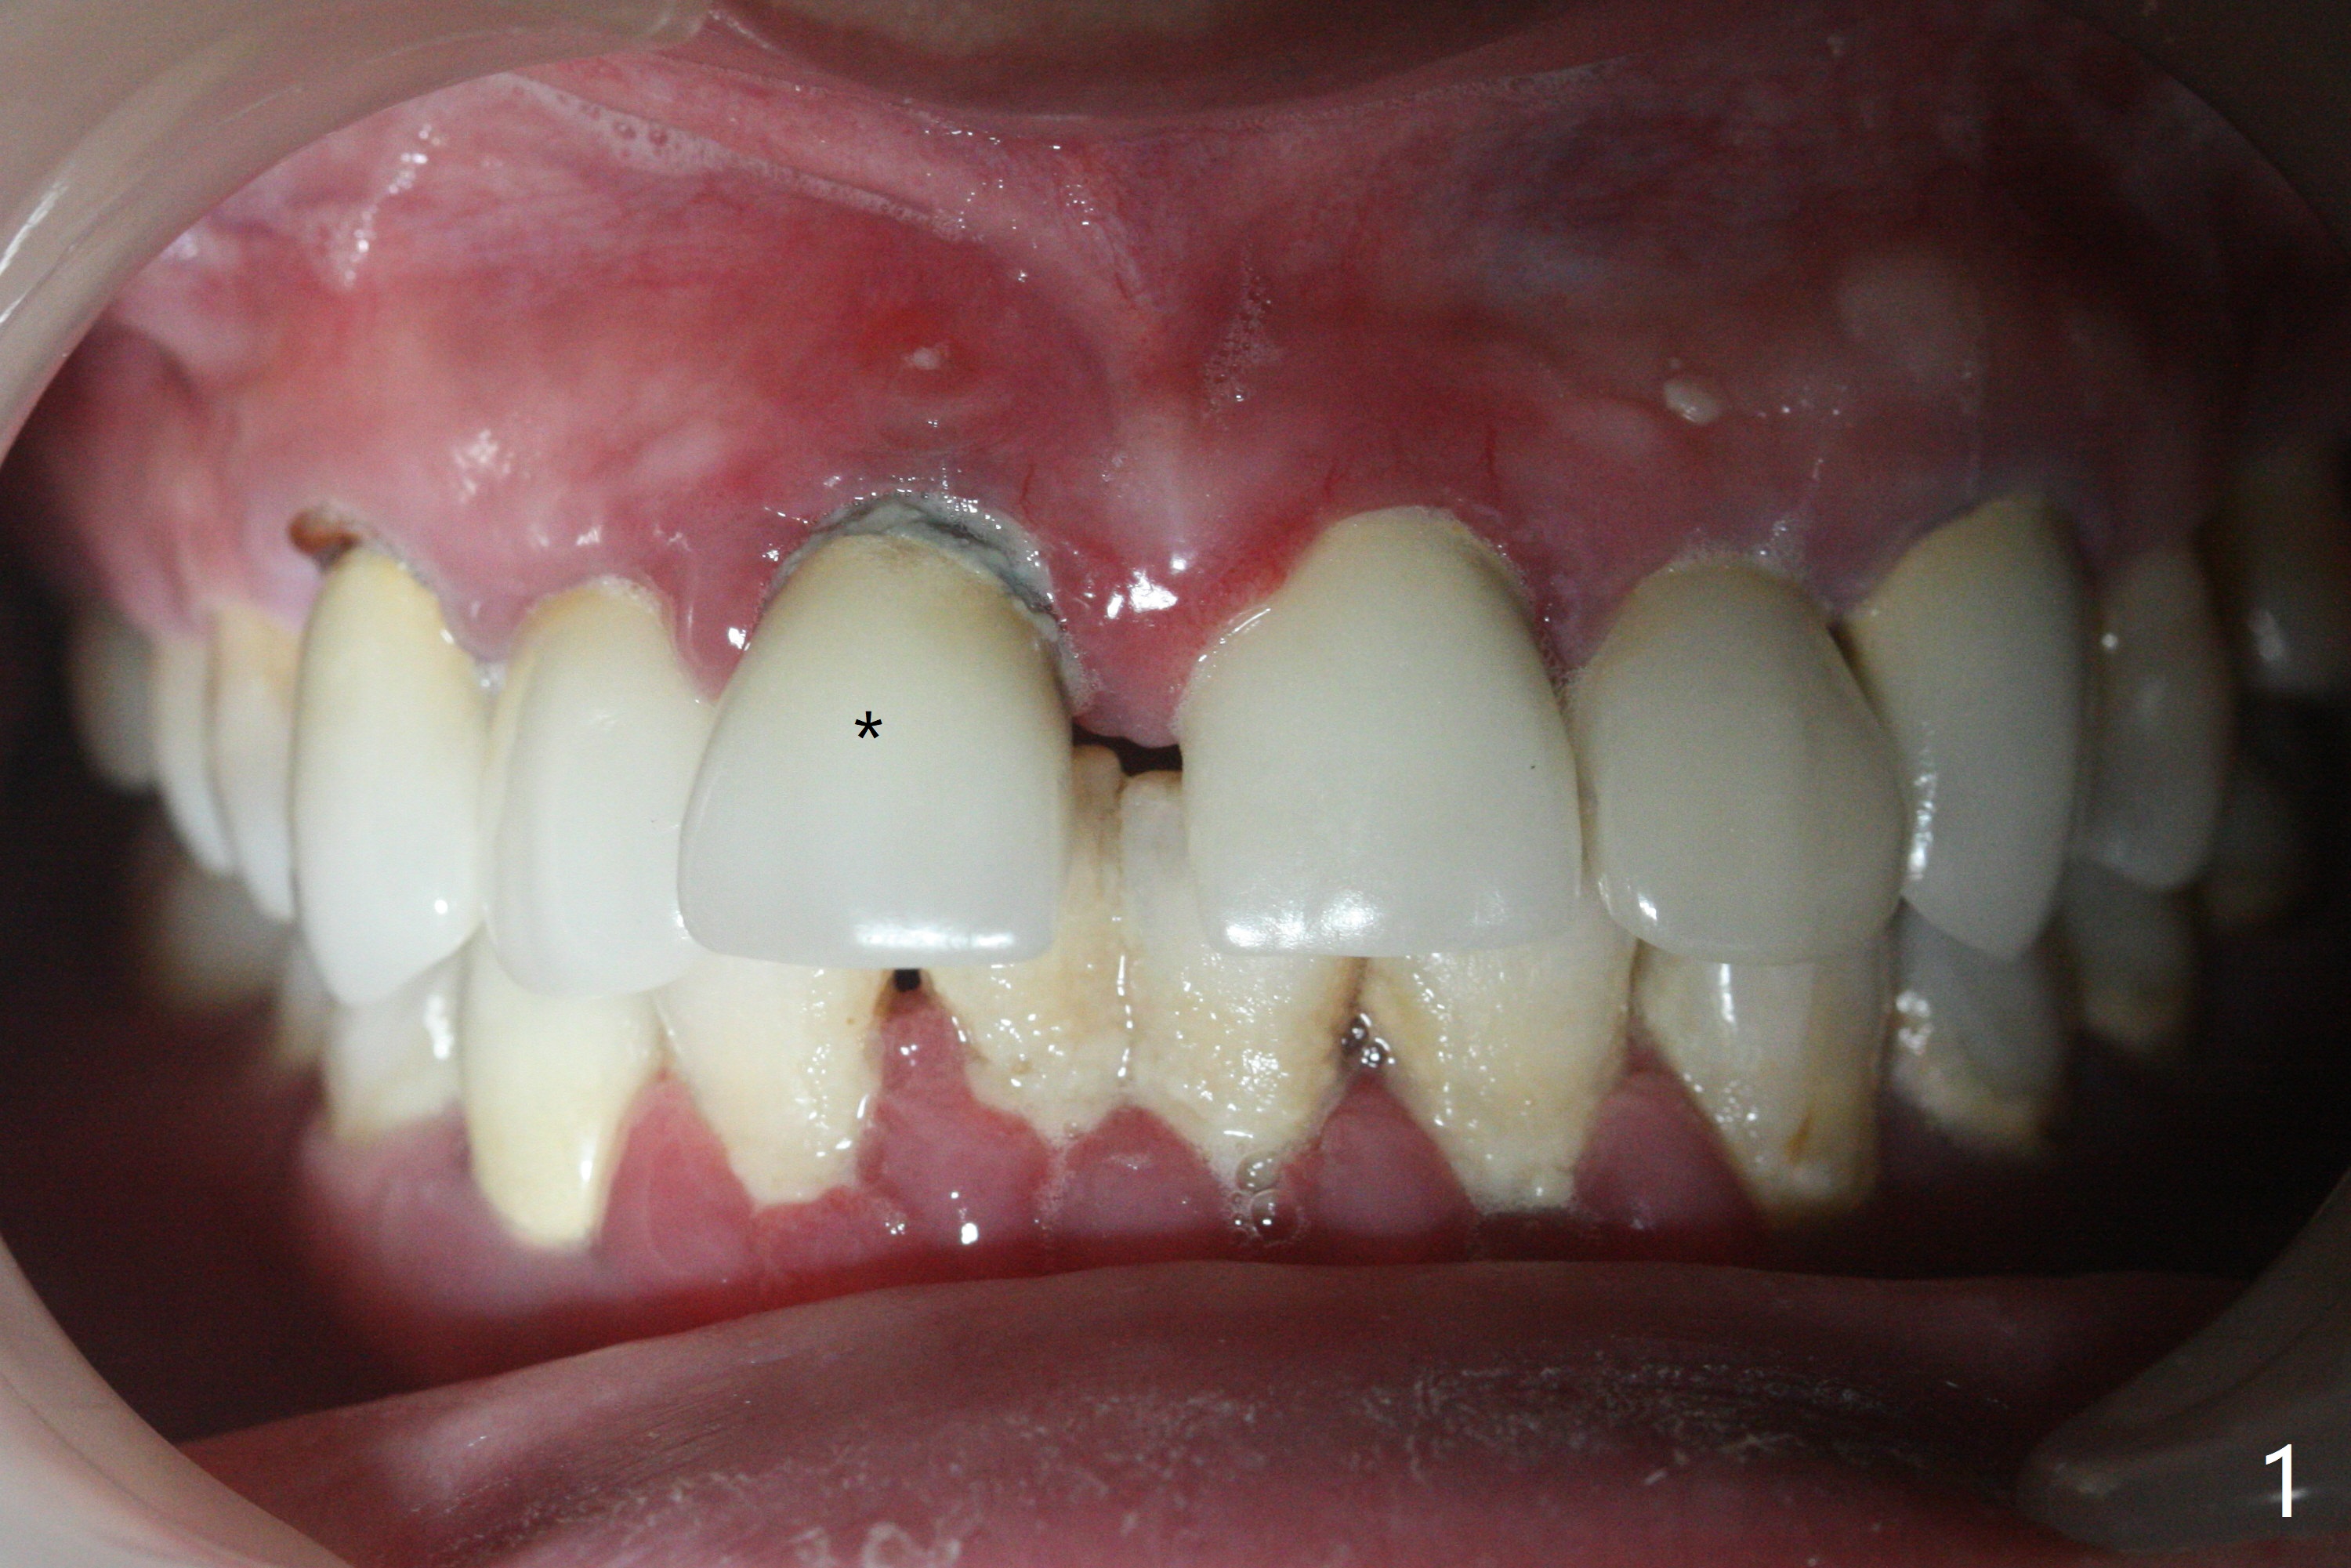

45岁女,害怕治疗,5年多没就医,右上1移位(图一(*),二),严重骨吸收(图三)。深洗后,即刻种植,由于牙龈7毫米长(图四,五)和使用粘性骨粉(骨壁再生),植体可以植浅些(图四:箭头)。上颌深洗一周后,除了患牙,牙龈红肿消除很多(图六,七)。